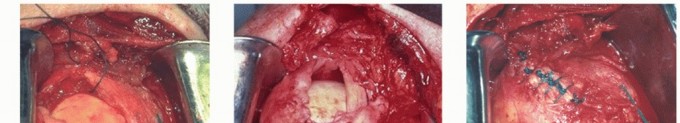

TECH FIG 5 • A. Filleted intra-articular portion of the tendon of the long head of the biceps. B. Biceps graft in place. (A: From Neviaser RJ. Tears of the rotator cuff. Orthop Clin North Am 1980;11:295-306; B: From Neviaser JS. Ruptures of the rotator cuff of the shoulder: new concepts in the diagnosis and treatment of chronic ruptures. Arch Surg 1971;102:483-485.)

This segment of tendon is filleted (

TECH FIG 5A

) and placed into the cuff defect. It is trimmed to fit the defect and contoured to accommodate it.

It is sutured side to side to the cuff and to a trough in the anatomic neck at the greater tuberosity, as described earlier (

TECH FIG 5B

).

After the described mobilization techniques have reduced the size of the defect as much as possible, the graft is reconstituted in sterile saline for 30 minutes so that it becomes soft and pliable (

TECH FIG 6A

TECH FIG 6 • A. Reconstituted freeze-dried cadaver rotator cuff graft. B. Reconstituted freeze-dried cadaver rotator cuff graft sutures in place. (A: From Neviaser JS, Neviaser RJ, Neviaser TJ. The repair of chronic massive ruptures of the rotator cuff by use of a freeze-dried rotator cuff. J Bone Joint Surg Am 1978;60A:681-684; B: From Neviaser R, Neviaser AS. Open repair of massive rotator cuff tears: tissue mobilization techniques. In: Zuckerman J, ed. Advanced Reconstruction: Shoulder. Chicago: American Academy of Orthopaedic Surgery, 2007:177-184.)

It is then trimmed and contoured to accommodate the free edge of the native cuff and then sutured to it with nonabsorbable no. 1 sutures.

It is also trimmed to reach a trough in the anatomic neck adjacent to the greater tuberosity and secured in the same fashion as the direct repair through drill holes in the bone or by anchors, as previously described (

TECH FIG 6B